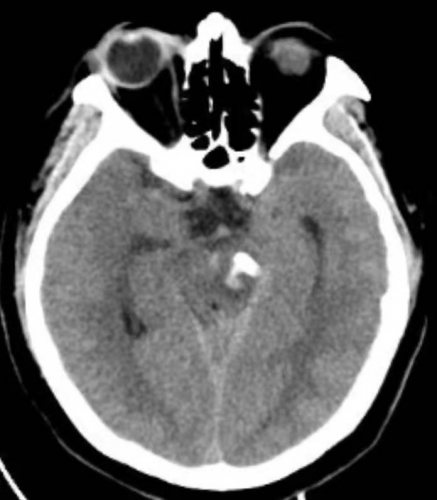

经CT检查诊断为高血压性脑干出血,出血量约13ml(图1),病情极其危重。经积极的术前准备,征得家属同意后,于住院11小时后,全麻下行经枕下脑干血肿微创置管抽吸术+侧脑室外引流术+微创气管切开急诊手术。手术历时1小时零15分钟,术后即刻复查头颅CT,见血肿清除90%(图2)。

图2:术后即刻CT